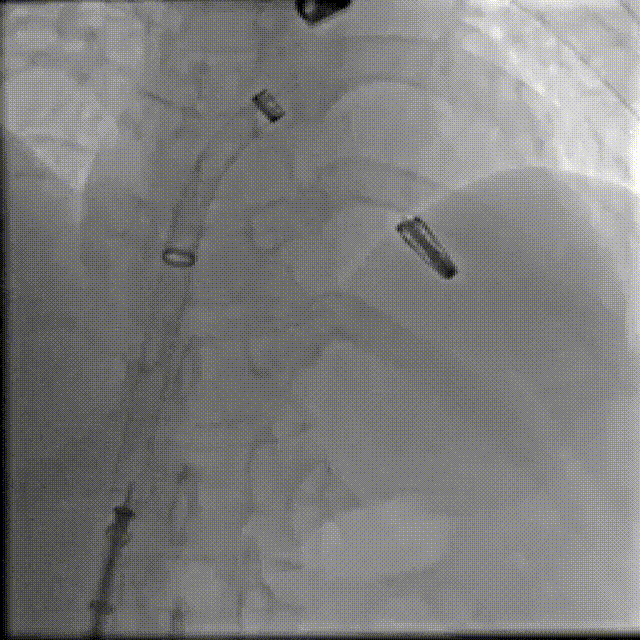

在阜外医院潘湘斌教授团队的支持下,手术经股静脉-房间隔入路,采用全身麻醉插管,在TEE和DSA引导下完成房间隔穿刺。置入JensClip瓣膜夹系统后,在左房调整瓣膜夹的位置和轴向,后进入左室,在TEE引导下捕捉二尖瓣前后瓣叶,并关闭瓣膜夹。经TEE反复确认手术效果后最终锁定并释放瓣膜夹。术后即刻超声显示瓣膜夹位置稳定,功能良好,二尖瓣反流由术前4+减少至微量,手术圆满成功。

术后DSA